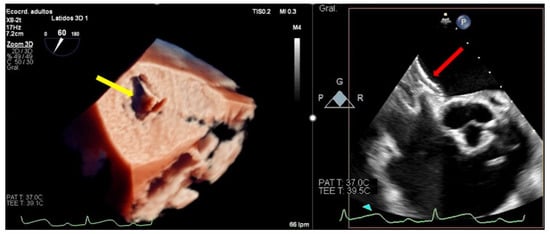

Complex mitral anatomy and several-clips implantation with suboptimal echocardiographic window due to the artefacts of the other clips, may be associated with clip embolization (Figure 6). Meticulous intra-procedural imaging with a clear visualization of the device, leaflets, and subvalvular apparatus reduces the risk of detachment.

Figure 6.

Clip embolization. (Left) Two-dimensional transesophageal echocardiogram showing a posterior leaflet prolapse (yellow arrow) after retrograde embolization of a clip to the right ventricle through the procedural atrial septal defect (red arrow). (Right) Fluoroscopy image at the end of the procedure showing two clips implanted in the mitral valve and another one embolized in the apex of the right ventricle (red arrow).